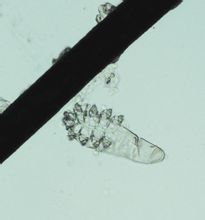

疥蟎生活史分為卵、幼蟲、前若蟲、後若蟲和成蟲五個期。疥蟎寄生在人體皮膚表皮角質層間,齧食角質組織,並以其螯肢和足跗節末端的爪在皮下開鑿一條與體表平行而紆曲的

蟎蟲顯微圖隧道,雌蟲就在此隧道產卵(圖32)。卵呈圓形或橢圓形,淡黃色,殼薄,大小約80×180μm,產出後經3~5天孵化為幼蟲。幼蟲足3對,2對在體前部,1對近體後端。幼蟲仍生活在原隧道中,或另鑿隧道,經3~4天蛻皮為前若蟲。若蟲似成蟲,有足4對,前若蟲生殖器尚未顯現,約經2天后蛻皮成後若蟲。雌性後若蟲產卵孔尚未發育完全,但陰道孔已形成,可行交配。後若蟲再經3~4天蛻皮而為成蟲。完成一代生活史需時8~17天。